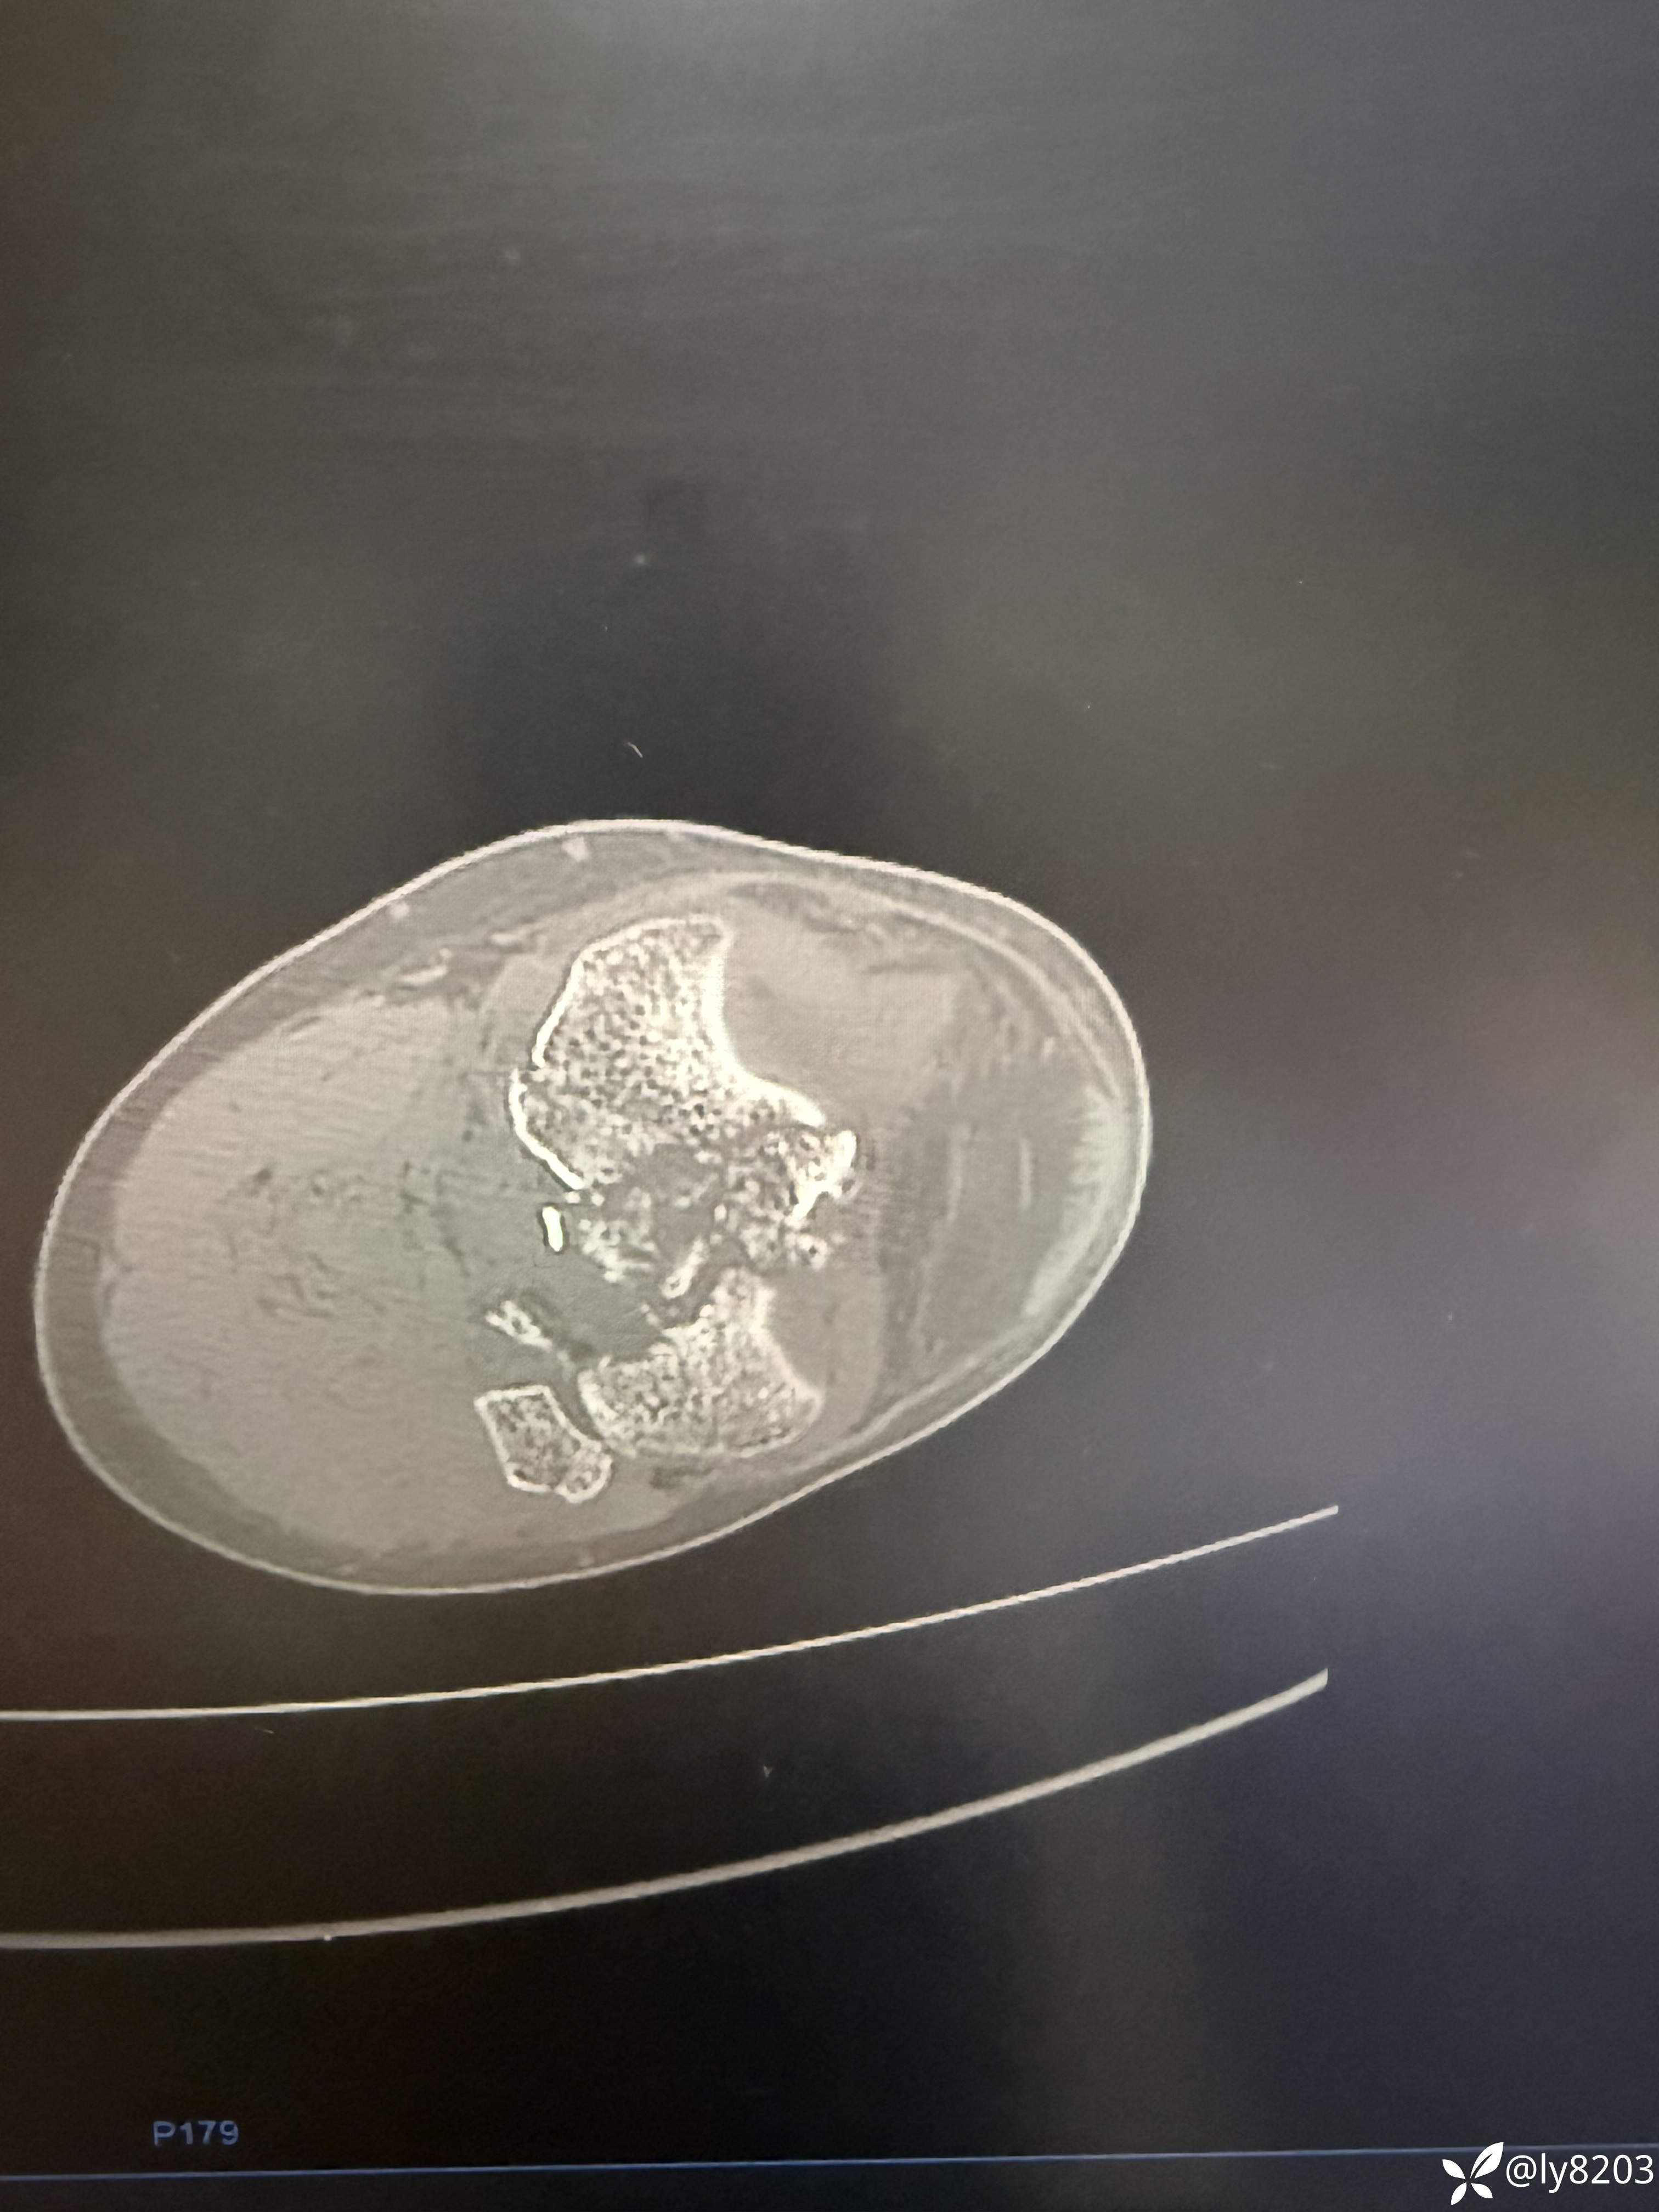

中年男子,外院转入患者,先看图

这个难点在后外侧游离骨块。按胡老师的方法,先将外侧平台用两个弯钳抬起,与前髁间棘对齐后克氏针固定,再从外侧副韧带后缘用骨拨托住并往前顶,从关节线用弯钳从前面抬,没成功,随即改变方案,用胡式顶棒外侧经皮顶,后侧骨块解剖复位,后缘与外侧平台丝滑对齐,克氏针固定。剩下就是常规操作了。以往都是大切口,截骨处理后外侧,胡教授的方法避免了切口大,创伤大。有利于加速康复。